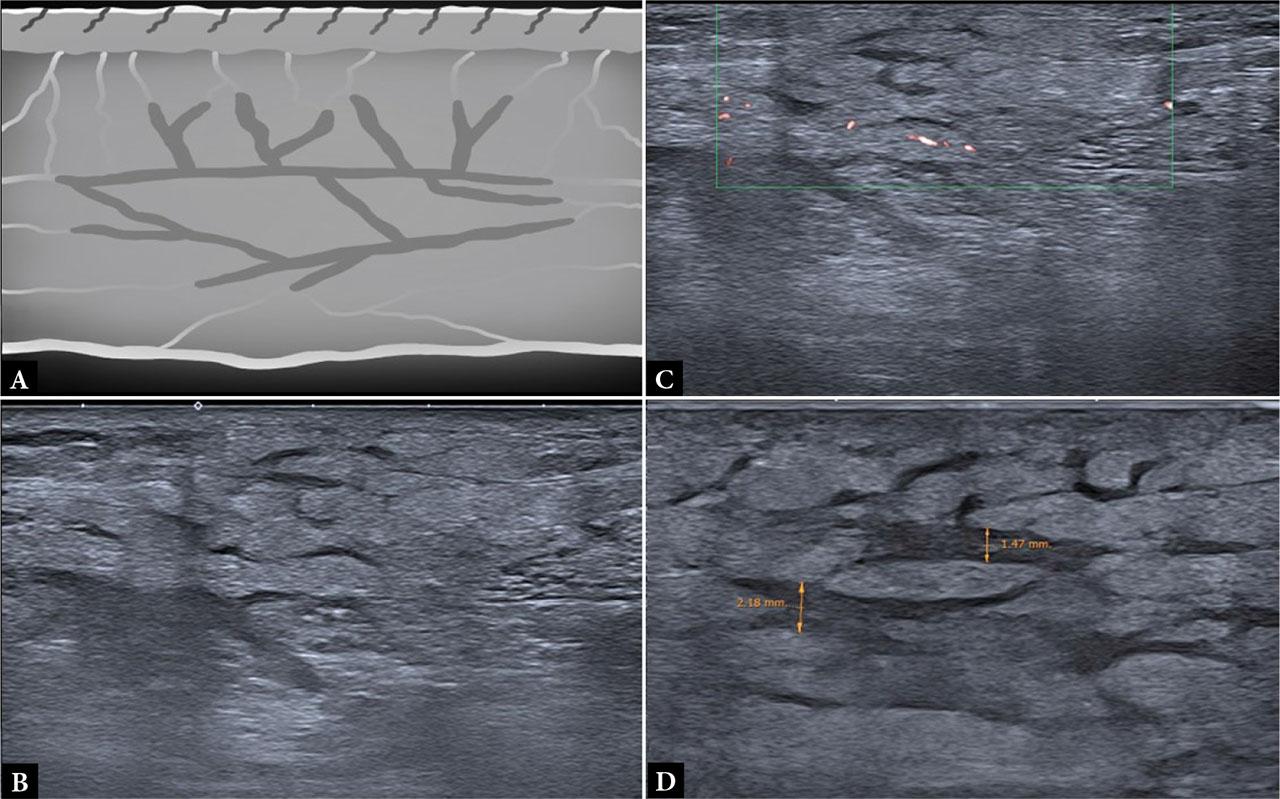

Predominantly septal panniculitis: the sonographic pattern is characterized by septal thickening and hypoechogenicity (thickness ≥1 mm in three or more septa), usually adjacent to non-compressible fat lobules. Hyperechogenicity of the adipose lobules is frequently present, along with an increase in Doppler flow. Together, these features produce a characteristic “jigsaw” appearance (Fig. 2).

Predominantly lobular panniculitis: the sonographic pattern lacks the typical features of septal disease. Instead, it shows hyperechoic, blurred adipose lobules with no significant increase in Doppler vascularity (Fig. 3).

Septal panniculitis sonographic pattern. A. Schematic drawing; B. Corresponding ultrasound image showing an area with poorly defined margins, prominent fatty lobules, interlobular septal thickening, and decreased echogenicity; C. Power Doppler ultrasound showing subtly increased vascularity; D. Same case examined with a 22 Mhz probe, demonstrating interlobular septal thickening (>1 mm)

Lobular panniculitis sonographic pattern: A. Schematic drawing; B. Poorly defined area in the SSAT with increased echogenicity and evanescent inter-lobular septa (white arrowheads); C, D. Poorly defined area of increased echogenicity in the SAT, with loss of lobular architecture, blurring of the dermo-hypodermic junction, and increased internal vascularity